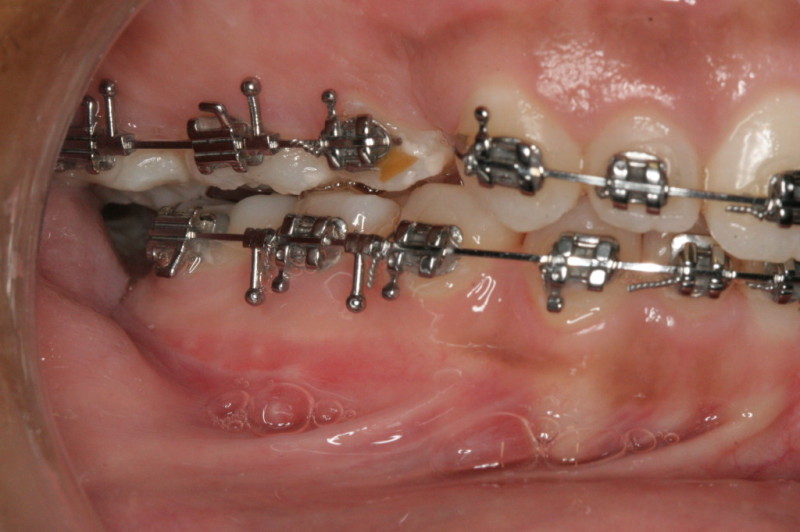

After Orthodontic Setup - Presurgical

Finished Patient with a Perfect Bite and Excellent Facial Proportions